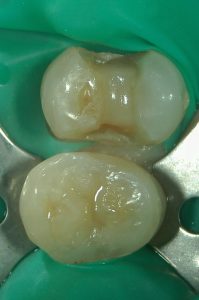

1 防湿・感染対策

唾液に触れる状況では細菌感染による治療成功率の低下や、接着が阻害されてしまう可能性があり、治療の確実性が落ちていまいます。

歯髄保存治療ではラバーダムというシートを歯にかけ、治療を行う歯に唾液や細菌がつかない治療環境をつくります。

2 むし歯の徹底除去

歯のための歯科治療には拡大下での施術が世界のスタンダードです。

確実なむし歯除去を行うため、また、必要以上に健康な歯を削らないため拡大鏡(ルーペ)や顕微鏡を用いむし歯治療を行います。

上の写真では下に位置する隣の歯に、侵襲・ダメージを最小限に抑えるためダイレクトボンディングを行っています。